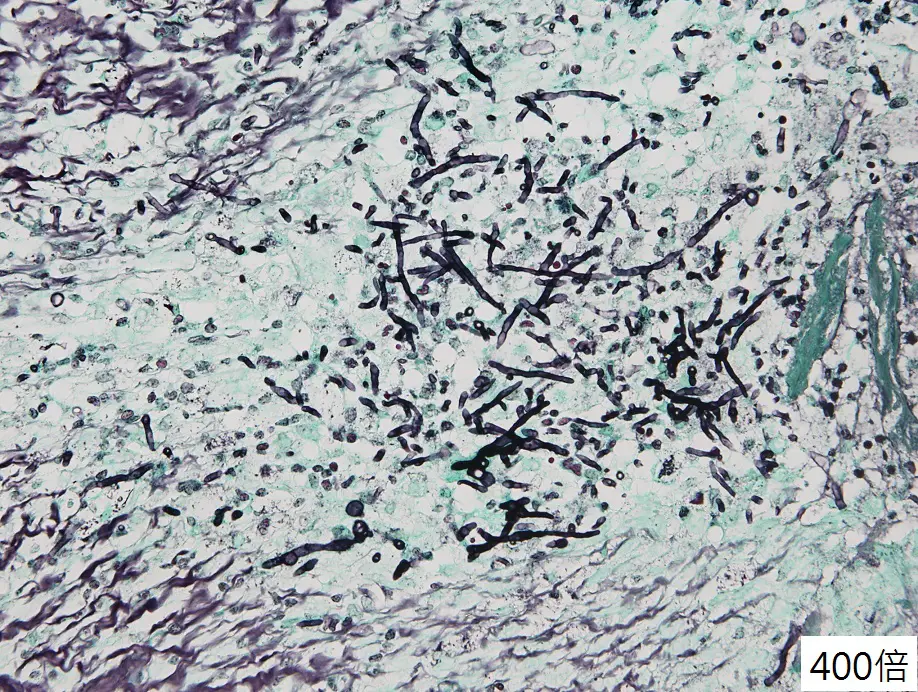

切片為400倍Gomori methenamine silver (GMS)染色。影像中見:

• 大量黑色菌絲呈細長管狀,寬度約3–5 µm。

• 菌絲具規則隔膜(septation),可見間隔分布。

• 菌絲分叉呈二叉狀分枝,多數分枝角度接近45°急性角。

• 未見寬大無隔膜之菌絲,也不見酵母或假菌絲結構。

上述形態符合Aspergillus spp.組織內典型表現。